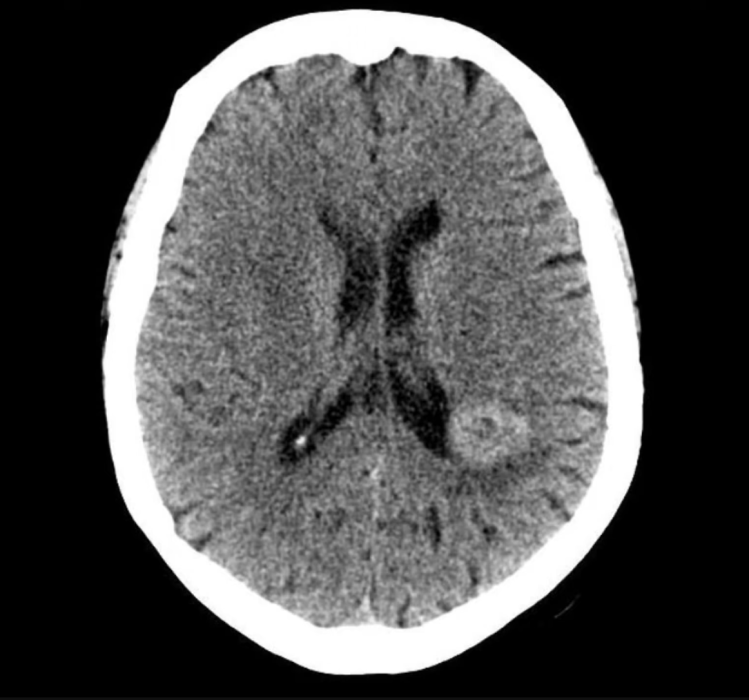

Sesler “Sende bir beyin tümörü var, bu yüzden beyin sapın iltihaplanmış. Hemen bir beyin görüntülemesine ihtiyacın var” deyince ve daha önce söyledikleri doğru çıktığı için onlara inanmış ve son derece rahatsız olmuş. Psikiyatristi ona güvence vermek için beyin tümörüyle ilgili herhangi bir fiziksel bulgusu olmadığını anlatmış, fakat emin olması için beyin görüntülemesi yaptıracağını belirterek bir beyin BT’si istemiş. Bu istek önce gereksiz bulunarak reddedilmiş, ama sonunda merkezdekiler ikna edilmişler ve BT çekilmiş. Sonuç herkes için şok ediciymiş. Beyinde büyük bir tümör (beyni örten zarlardan kaynaklanan ve yavaş büyüyen bir frontal parafalcine menenjioma) bulunmuş.

Tümörün büyüklüğüne rağmen kadında hiç baş ağrısı, güçsüzlük, konuşma problemi ya da herhangi bir nörolojik kusur yokmuş. Beyin cerrahları beklemeleri mi, yoksa hemen ameliyat etmeleri mi gerektiğini tartışmışlar ve sonunda hasta ve yakınlarıyla birlikte ameliyata karar vermişler. 4X6,5 cm kadar ölçülen tümör tamamen çıkarılmış. Kadın daha sonra anesteziden uyandığında sesleri son bir kez daha duyduğunu anlatmış: “Sana yardım edebilmiş olmaktan dolayı memnunuz. Hoşçakalın” deyip bir daha geri dönmemişler. Hastanın antipsikotik ilacı hemen kesilmiş. Ameliyattan sonra ne varsanısı, ne sanrısı, ne de başka bir psikiyatrik semptomu olmuş.